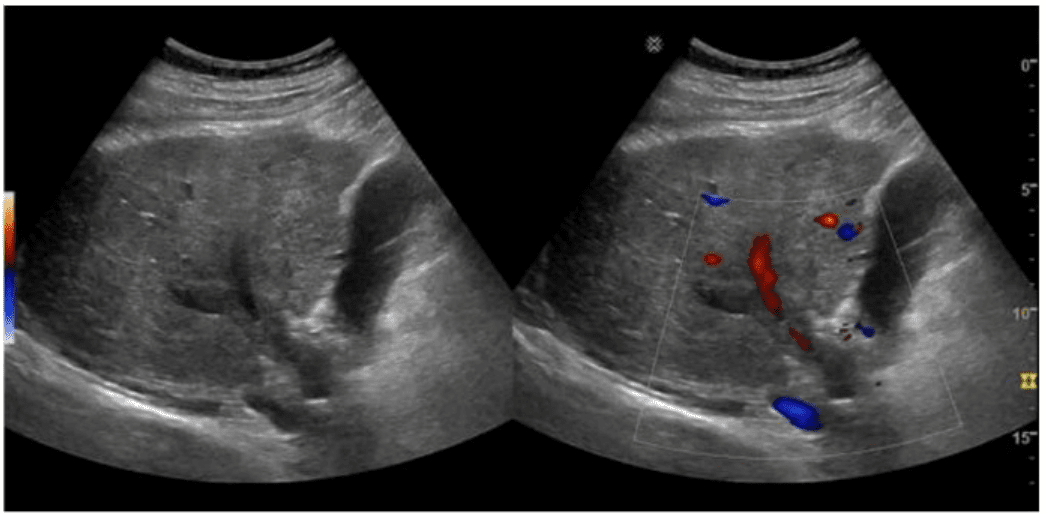

Which clinical indication is most consistent with the finding depicted in this image?